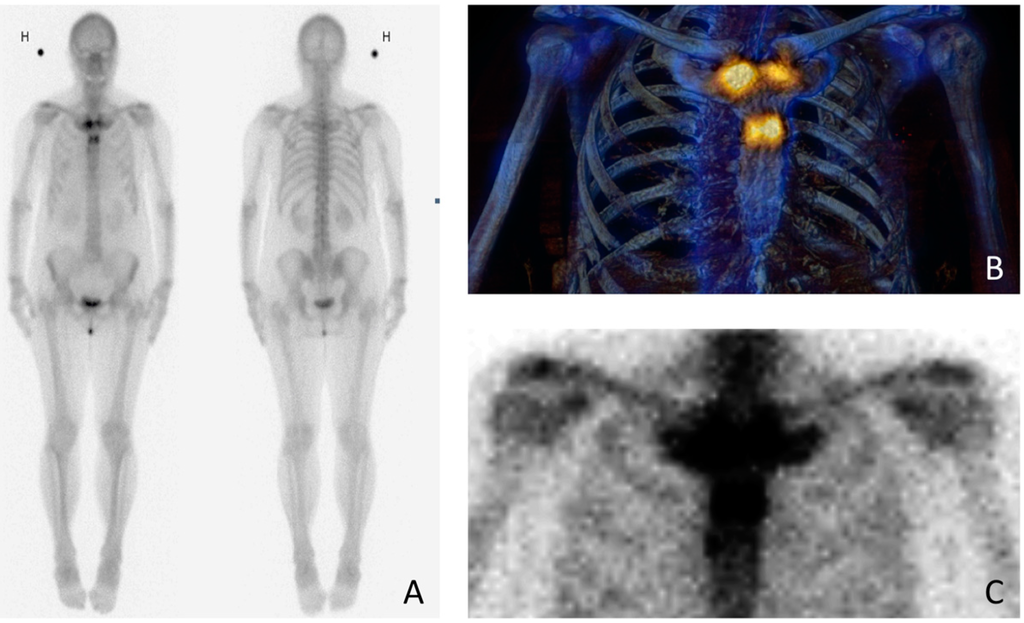

Figure 2. To rule out malignancy, the patient was examined with whole-body bone scintigraphy with both planar (A) and single photon emission computed tomography (SPECT) (B)/low-dose computed tomography (CT) images (C). Scintigraphy was performed in 2015, within two weeks of the chest radiograph (Figure 1A). The images demonstrate abnormal radiotracer activity in both sternocostoclavicular joints, in the sternal angle and manubrium and also in the proximal body of the sternum. The symmetric tracer activity adjacent to the joints rules out malignancy; instead, scintigraphy shows a typical “bullhead sign” [7]. The bullhead sign consists of increased scintigraphic activity in the sternal manubrium and in the adjacent clavicles and ribs, representing the skull and horns of the bull, respectively. The increased scintigraphic activity corresponds to the radiographic changes caused by the hyperostosis. The bullhead sign is a characteristic scintigraphic pattern in demonstrating SCCH [7,8,9]. H stands for højre (Danish) = right side of the patient. The possibilities of diagnostic imaging are wide. Chest radiographs, Tc-99 m bone scintigraphy, computed tomography (CT) or magnetic resonance imaging (MRI) are all used to various extent [4,5,7,10]. Whole-body bone scintigraphy and MRI (including T1-weighted (T1W), short tau inversion recovery (STIR) with or without T1W post-gadolinium sequences) have both proven to be of great importance where radiographically occult sites hamper the diagnosis [5,7]. In case of extensive follow-up imaging, MRI has the advantage of being radiation-free.